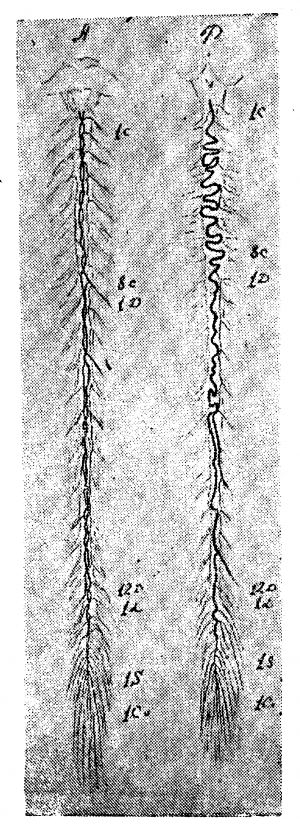

Вены вещества спинного мозга (рис. 1). Центральные вены, подобно артериям, бывают правые и левые, то есть выносят кровь из (какой-либо одной половины серого вещества. В отличие от соответствующих артерий, они анастомозируюг между собой. Возникают они из мелких веточек, близких по калибру к артериолам, и сами являются очень мелкими тканевыми сосудиками. Поллак отмечает, что в сером веществе спинного мозга очень редко встречаются относительно более крупные венозные сосуды: мелкие веточки почти непосредственно собираются, в относительно крупный стволик центральной вены. Центральные вены впадают в передние венозные тракты или вернее они образуют их. Вены белого вещества спинного мозга крупнее соответствующих артериол и центральных вен (вен серого вещества). В отличие от артерий вены серого и белого вещества богато анастомозируют между собой, так что кровь из серого вещества может изливаться двумя путям: через передние и через боковые и задние тракты, чем и объясняется относительно малый калибр вен серого вещества и кажущееся нарушение правила о превосходстве площади сечения вен над площадью сечения соответствующих артерий.

Вены поверхности спинного мозга (рис. 2). Вены мягкой мозговой оболочки, как и артерии, расположены преимущественно продольно, но число венозных стволов гораздо менее постоянно, чем артериальных. Даже на одном препарате на разных уровнях оно различно. Вены змеятся вдоль спинного мозга, иногда сплетаясь в «нераспутываемый клубок», как выражается Адамкевич. Строго говоря, на поверхности спинного мозга существует настоящее венозное сплетение, аналогичное сплетениям позвоночного канала. Число, калибр и расположение отдельных стволов венозного сплетения спинного мозга подлежат очень большим колебаниям.

Передний венозный тракт (Tractus venosus anterior medullae spinalis seu venae comitantes arterias anlteriores Kadyi — vena spinalis mediana anterior Adamkewiczi). Описание этого тракта у разных авторов вариирует. По описанию Адамкевича и Кадыя, он начинается от венозного сплетения продолговатого мозга и идёт вдоль всего спинного мозга, не очень точно и строго сопровождая передний артериальный тракт.

Кадый обычно находил его более погружённым в переднюю борозду, нежели соответствующая артерия, очень часто удвоенным, даже утроенным и обвивающим сопровождаемую артерию.

Адамкевич считает его гораздо менее тесно связанным с артерией, легко отклоняющимся в стороны от средней линии; автор подчёркивает большую неравномерность калибра, тракта на разных уровнях. Пополняется тракт, главным образом, из центральных вен, значительно менее из вен передней поверхности. На своём протяжении он даёт большие ветви, соответствующие артериям передних корешков. Адамкевич называет эти ветви передними спинальными венами; число их обычно превосходит число соответствующих артерий. Подобно артериям, они качественно и количественно наиболее выражены в области утолщений спинного мозга, в тех самых местах, где наиболее развиты и артерии передних корешков. В области поясничного утолщения, как правило, бывает 1—2 более крупных сосуда, соответствующих таким же артериям. Адамкевич описал их под названием «передние большие боковые спинальные вены»; автор отмечает, что «в большинстве случаев существует одна большая передняя вена, обычно сопровождающая 2-й—3-й поясничный или 1-й крестцовый корешок, почти с одинаковой частотой то справа, то слева. Вены эти не ветвятся». «Нет никакого сомнения, — продолжает Адамкевич, — что подобно тому, как спинальные артерии служат для притока крови, спинальные вены служат для её оттока. Они уносят кровь из передней средней вены... в межреберные, поясничные и крестцовые вены... Через каждую спинальную вену поток крови оставляет спинной мозг, слагаясь из потоков противоположных направлений сливающихся отрезков средней вены. С этим согласуется и то, что средняя вена значительно расширяется с обеих сторон, приближаясь к каждой спинальной вене, и что каждая спинальная вена сильнее обоих прилегающих к ней отрезков средней вены» (Адамкевич, ч. II, стр. 123—124).

Передний венозный тракт заканчивается вместе с конечной нитью спинного мозга. Нижние крупные оттоки переднего тракта принято называть передними венами Адамкевича.

Вены задней поверхности спинного мозга. Описания вен задней поверхности спинного мозга, сделанные различными авторами, также существенно отличаются друг от друга.

Кадый так формулирует свои наблюдения: «Постоянным и до известной степени типичным образованием можно считать заднюю венозную цепь. В пояснично-крестцовом отделе спинного мозга она является единственным и значительным венозным стволом. В шейной части также всегда можно найти продольный главный средний ствол, даже когда наряду с ним появляются заднебоковые венозные цепи. В грудном отделе средний главный ствол является если не единственным, то во всяком случае наиболее значительным венозным сосудом. Иногда калибр его сильно мельчает или сосуд совсем прерывается. Вследствие этого сбоку от средней линии появляются более или менее мощные стволы, расположенные различным образом. Их нужно рассматривать как разветвления средней венозной цепи, а не как равноценные ей самостоятельные образования» (стр. 78).

Адамкевич считает, что принцип построения вен задней поверхности спинного мозга вполне соответствует принципу построения вен передней поверхности. «Это обстоятельство, — замечает Адамкевич, — тем более достойно внимания, что артериальные сети передней и задней поверхности спинного мозга существенно различны» (стр. 125). Помимо среднего ствола, Адамкевич описывает и боковые стволы под именем «задние боковые спинальные вены».

Средний задний венозный тракт вверху впадает в вену заднего корешка первого спинномозгового нерва или же в вену XI и даже X черепномозговой пары. Но иногда он и непосредственно вливается в вены позвоночника, прободая твёрдую мозговую оболочку по средней линии или же предварительно разделяется на два стволика и прободает оболочку по сторонам от средней линии. Как и передний тракт, задний наиболее силён в шейном и поясничном утолщении, ход его гораздо более извилист, чем переднего тракта. В своём хвостовом конце он вливается в одну-две вены задних корешков, в большинстве случаев, как это описал Адамкевич, в вены 12-го грудного или 1—2-го поясничных корешков. Но тракт может и здесь непосредственно прободать оболочку. Нижние оттоки тракта независимо от того соединены ли они с корешковыми венами или нет, Адамкевич называет «задними большими спинальными венами». Их постоянство подтверждается и другими исследователями. Так, Словохотов хорошо видел задние вены (и артерии) Адамкевича у плодов в возрасте 6—7 лунных месяцев.

Задние боковые спинальные вены (Адамкевич). Обе задние продольные боковые венозные цепи сильнее и постояннее соответствующих передних. В поясничной н крестцовой области они бывают двойными с обеих сторон, причём крайняя цепь идёт впереди входа корешков. Кадый отрицает этот факт и считает, что задние боковые артерии не сопровождаются соответствующими венами. Боковые вены возникают из вен белого вещества спинного мозга, выходящих на поверхность по линии задних корешков.

В шейной области выше утолщения боковые продольные вены распадаются в венозную сеть, покрывающую заднюю поверхность спинного мозга по обе стороны от средней продольной вены, с которой боковые многократно анастомозируют по всему длиннику мозга. Число сосудов, уносящих кровь из продольных вен, непостоянно. Они неравномерно распределяются по сторонам и по длиннику мозга. Вены задней поверхности богато анастомозируют с венами передней поверхности. Адамкевич называет их «задними спинальными венами».